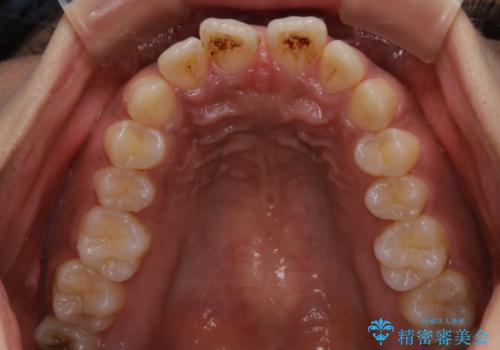

インビザライン矯正 歯を抜かずに出っ歯を改善!

- 出っ歯と前歯の隙間が空いていることを気にされて来院されました。

また、自然な感じで口元を下げていとのことでした。

奥歯のかみ合わせが問題なかったため、上顎の前歯の隙間を閉じるとともに、上顎の歯の側面を削ることをメインにして、出っ歯を改善する治療計画としました。

上顎の歯の傾きを変えるうえで、下顎の歯とのバランスのことも考え、下顎の歯の側面も削ることを加えています。

また、今回は口元を変えたい中に、劇的な変化は避けたいとのことだったので、抜歯をしない計画としています。

抜歯をしない場合、口元の変化は感じにくいですが、前歯の傾きが変わることで、口の閉じやすさは感じていただけたとのことです。

症例にもよりますが、本症例は奥歯のかみ合わせに問題がなかったので歯の側面を削ることメインに、前歯の傾きを改善することができました。

抜歯を行う場合や抜歯をしなくても奥歯の位置をずらす場合は、治療期間が長期化することが多いですが、今回は歯を削ることで改善できたため、短期間で治療を完了することができました。